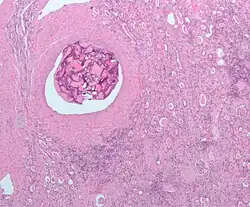

Tomografia komputerowa jest podstawową metodą oceny stopnia zaawansowania guza nerki. W TK wzmocnienie kontrastowe jest oceniane za pomocą porównania obrazu zmiany przed i po podaniu kontrastu. Wzmocnienie sygnału >20 j.H. (jednostek Hounsfielda) wskazuje na wzmocnienie kontrastowe, które przemawia za obrazem guza nerki[2][61][62][63][64].